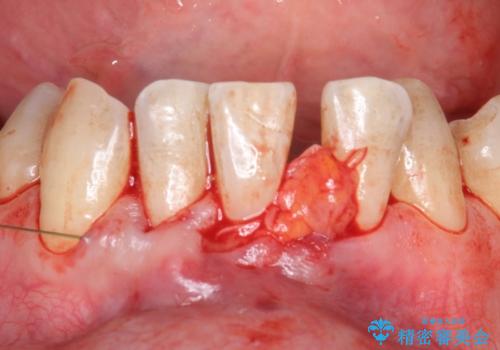

- 矯正前に下顎前歯の歯肉退縮の改善と予防のために歯肉移植を行った症例です。

上顎口蓋部から結合組織を採取し、下顎前歯部に移植しました。